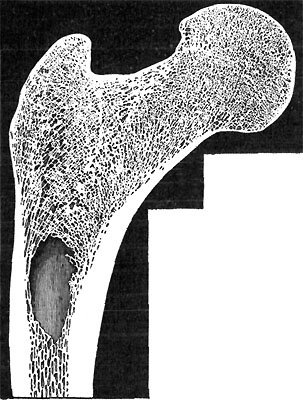

214 Lengthwise Section of Bone

214 Cross Section of Bone